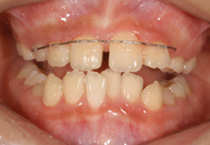

Case 2

Smile Line case 2 2022.08.28

2022.08.28